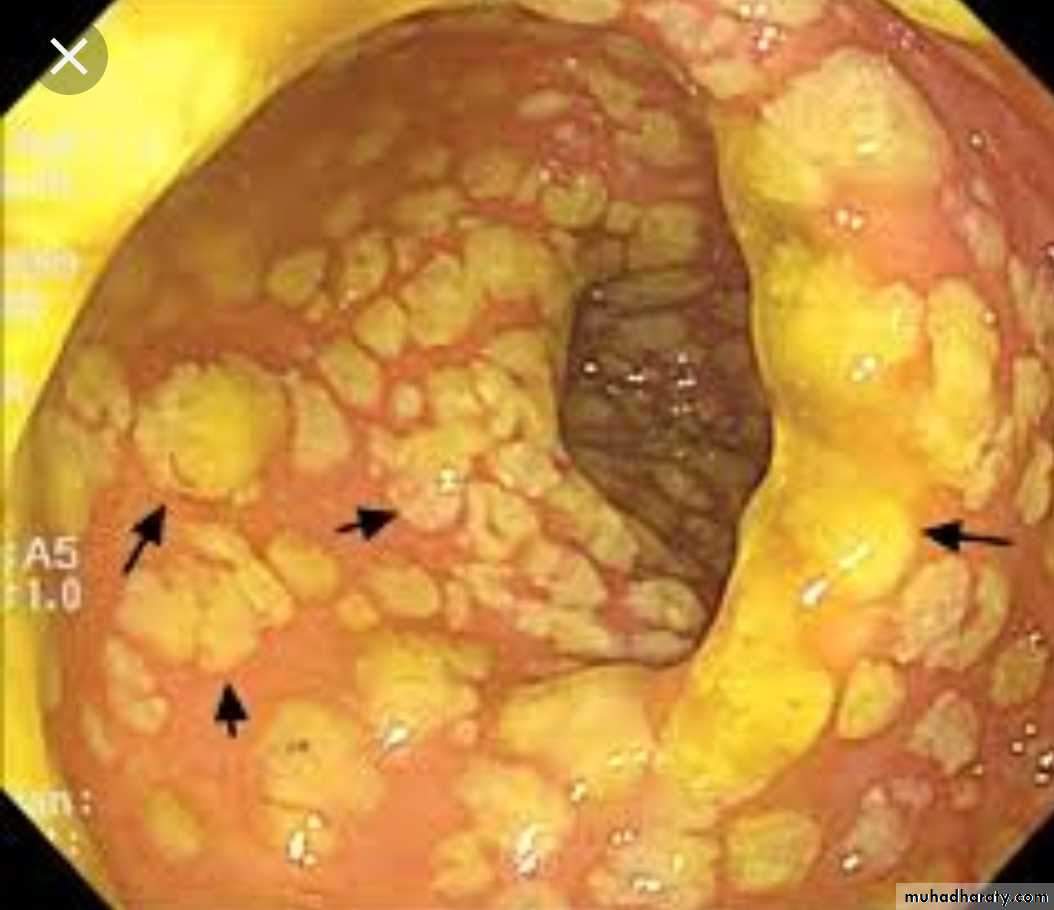

Pseudomembranous colitis

Yellow-white mucosal plaques or pseudomembranes

Denuded epithelium with mucopurulent exudate erupts out of crypts to form a mushroom-like cloud of necrotic debris & neutrophils that adheres to surface